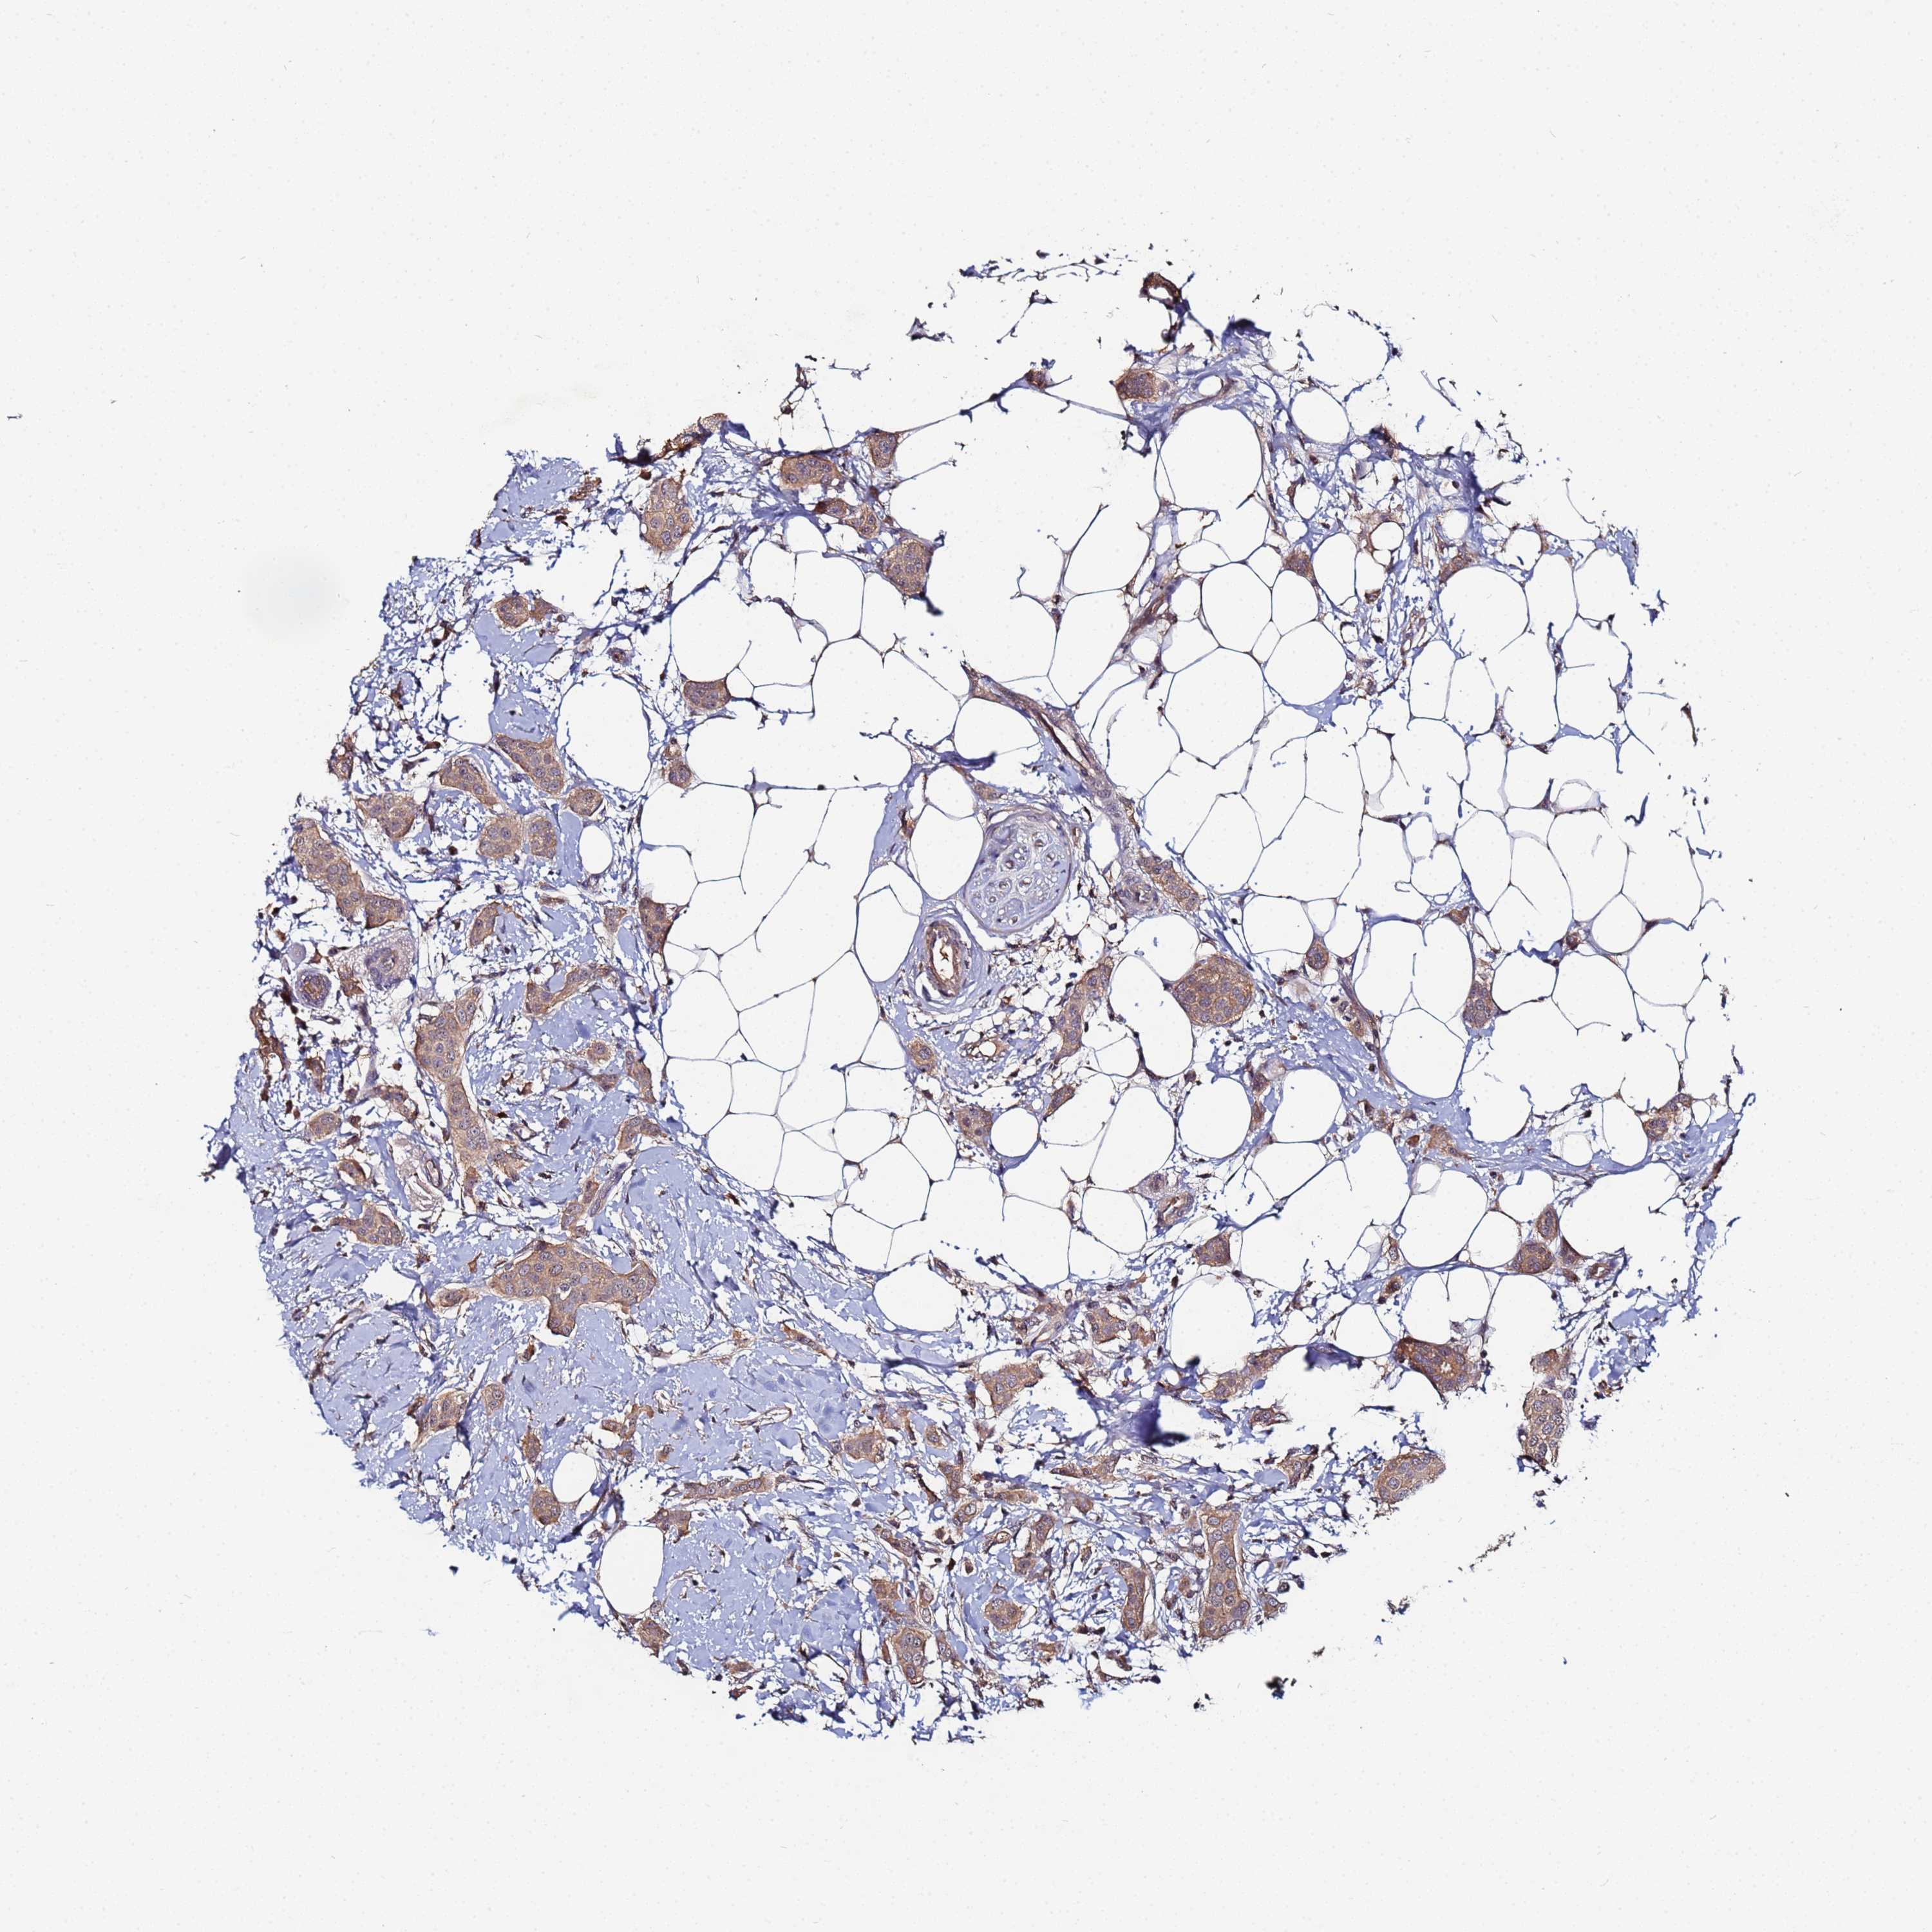

CANCER BREAST CANCER Show tissue menu

BRCA TCGA BRCA VALIDATION PROTEIN EXPRESSION